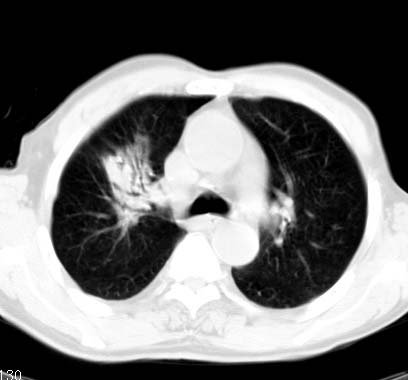

标题: CT14027:男性病人 71岁 咳嗽咳痰数周. [打印本页]

标题: CT14027:男性病人 71岁 咳嗽咳痰数周.

男性病人 71岁 咳嗽咳痰数周.诊断结核应该有保障吧!

结核是要考虑,但肺癌也不能排除.

右上肺结核,请结合痰检除外活动期;右上叶支气管官腔狭窄建议支气管镜或抗僗后随诊除外堵塞性改变。

高度怀疑肺癌,强烈要求纤支镜检查。